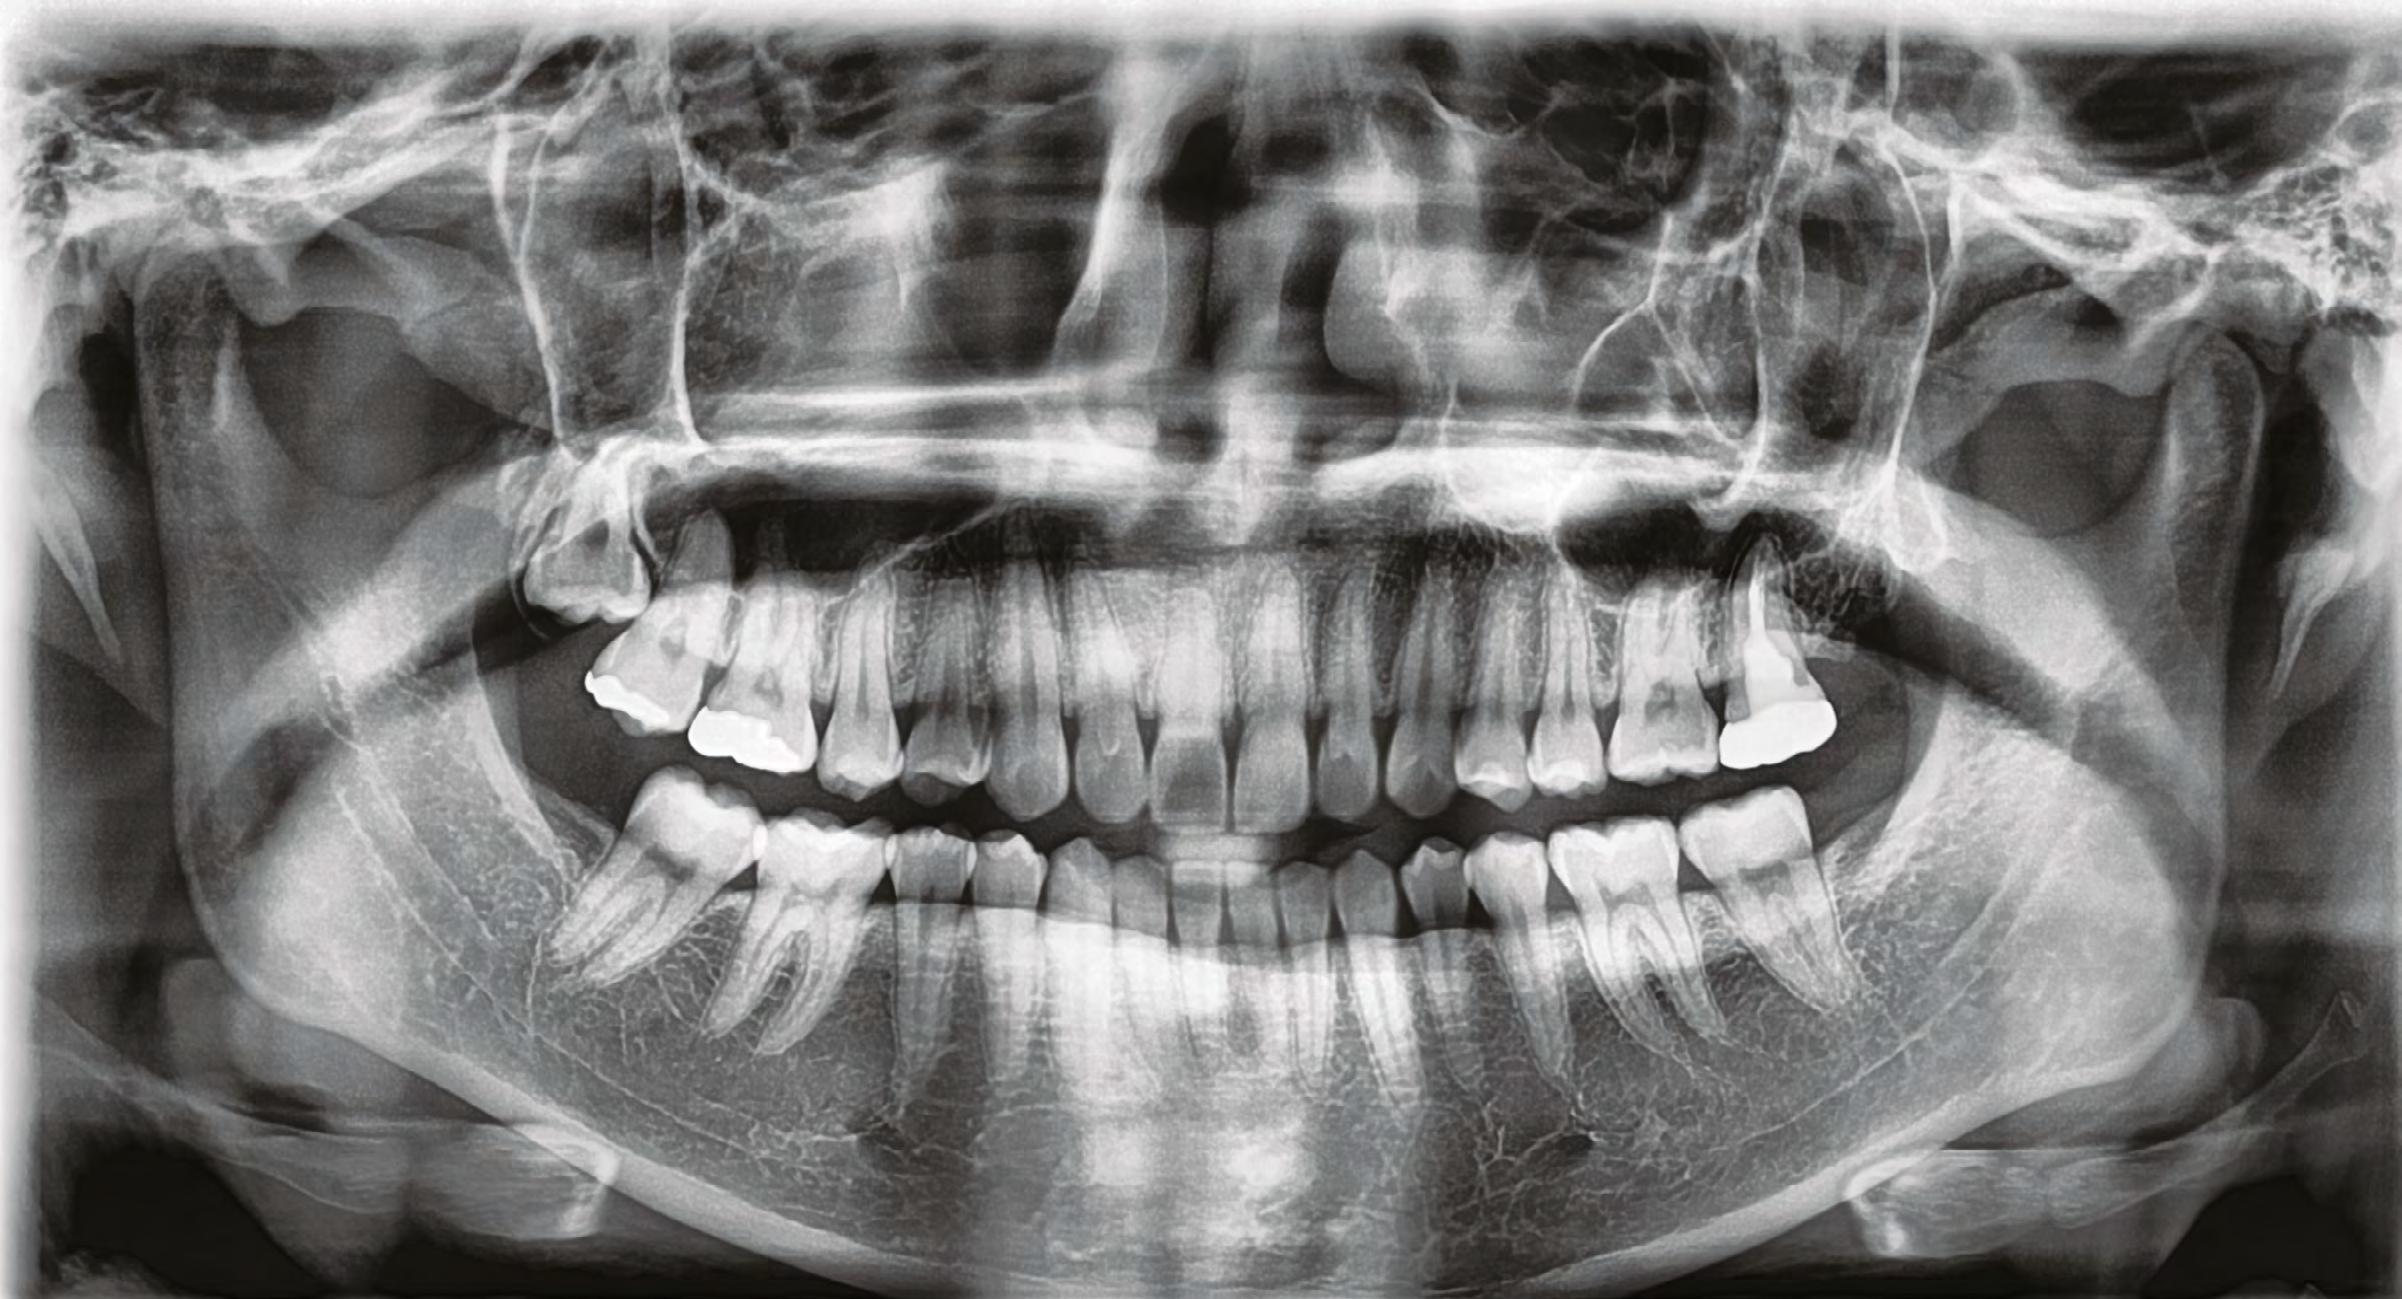

52 | SONRIENDO AL FUTURO

Tratamiento ortodóncico en paciente adulto tratado con extracciones de primeros molares permanentes. Reporte de caso